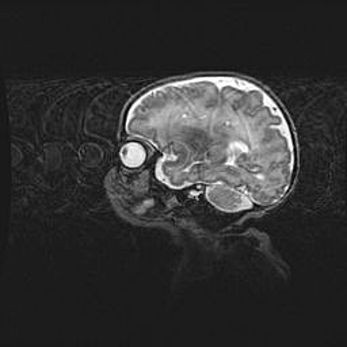

Мальформация Денди-Уокера. Киста задней черепной ямки.

Агенезия мозолистого тела.

Возраст: 2,5 месяца

Вес: 2420 г

Пол: женский

Окружность головы: 37 см

Срок гестации: 32 недели

Мальформация Денди—Уокера — редкий вид патологии ЦНС, представляющий собой врожденный порок развития каудального отдела ствола и червя мозжечка, ведущий к неполному раскрытию срединной (Мажанди) и латеральных (Лушка) апертур IV желудочка мозга. Для этогно синдрома характерна триада симптомов: гипотрофия червя мозжечка и/или полушарий мозжечка, кисты задней черепной ямки, гидроцефалия различной степени. В 70% случаев порок сочетается и с другими аномалиями головного мозга, в частности с агенезией мозолистого тела.